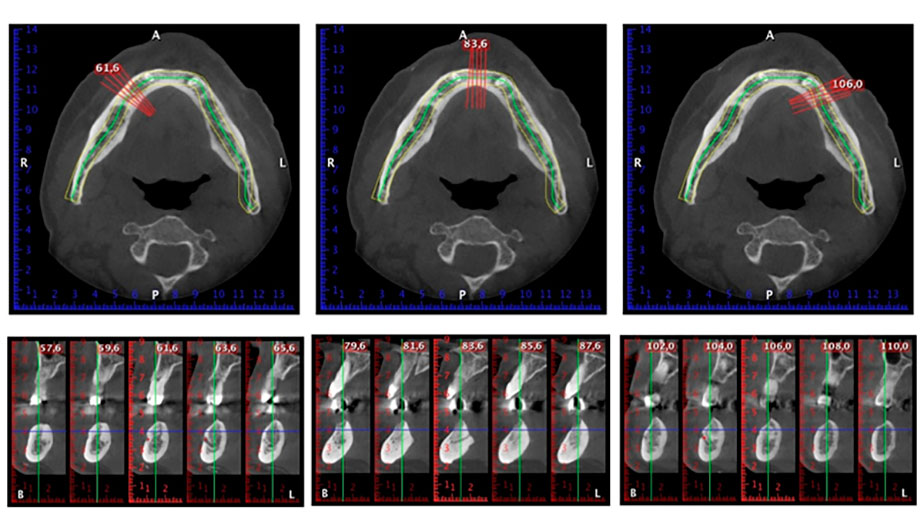

A three-dimensional cone beam computed tomography scan (CBCT, Planmeca) was performed to aid planning and minimize risks. This revealed that the quality and quantity of the available bone were sufficient for the surgery and immediate restoration using the Fast & Fixed method. Following the protocol for this concept, the implants are inserted at 35, 32, 42 and 45. Angling the distal implants by up to 45° shifts the emergence profile to posterior and generates a larger support polygon (Fig. 3).

Fast & Fixed method

Fig. 3